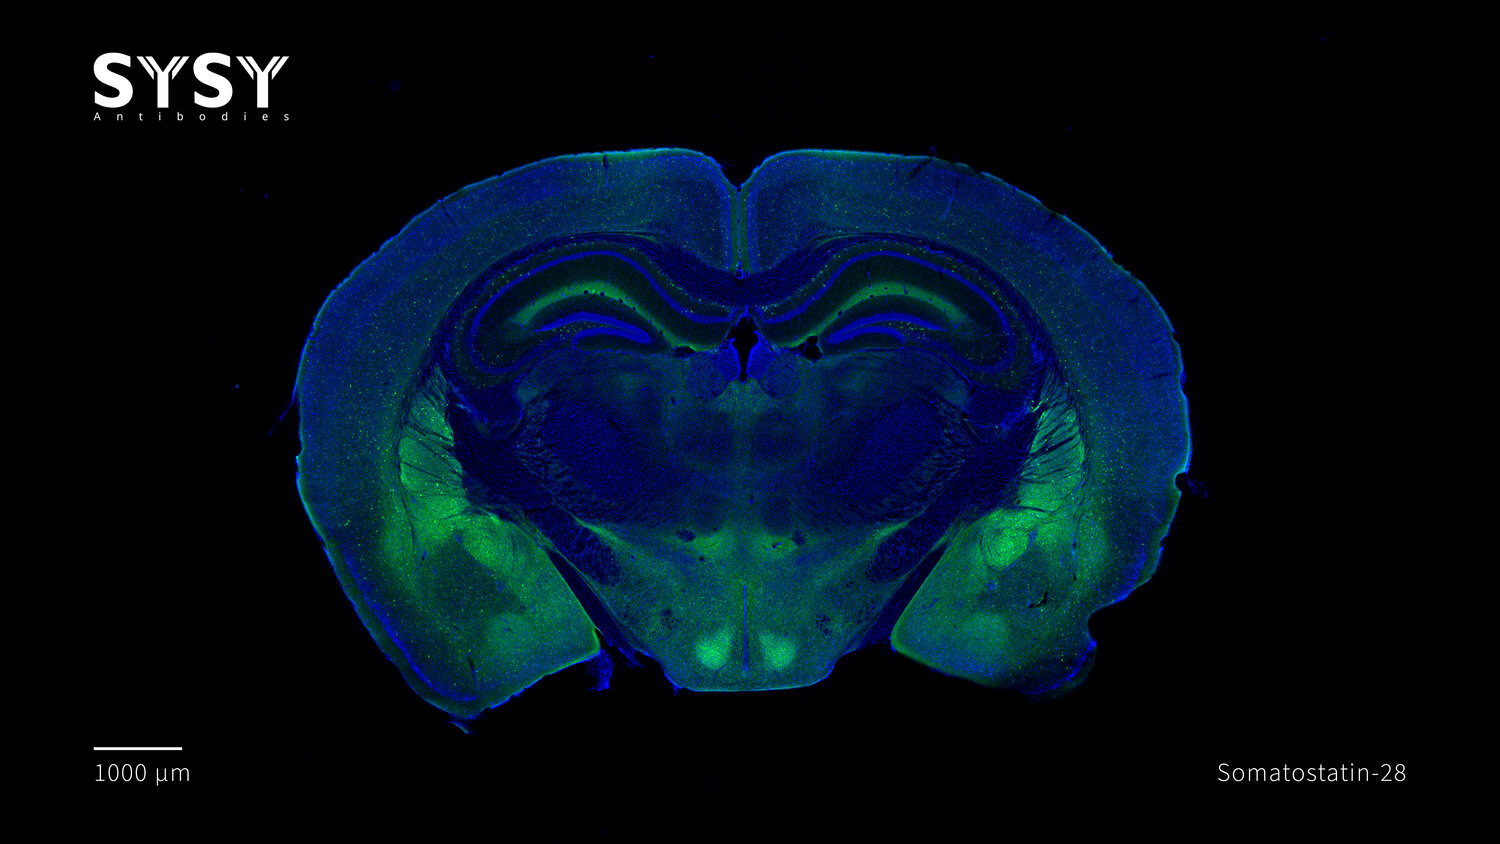

Somatostatin-28 antibody - 366 017

ICC: 1 : 500 up to 1 : 2000 gallery

IHC: 1 : 500 up to 1 : 1000 gallery

IHC-P: 1 : 100 up to 1 : 1000 gallery

Specificity The antibody detects somatostatin-28. It also recognizes the unprocessed precursor protein. It does not bind to somatostatin-14.